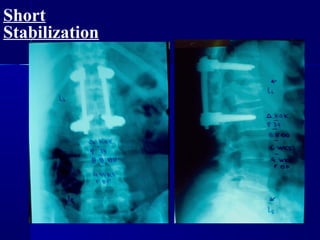

Short

Stabilization

LLoonngg ssttaabbiilliizzaattiioonn

OOnnee lleevveell aabboovvee aanndd bbeellooww

tthhee ffrraaccttuurreedd vveerrtteebbrraa